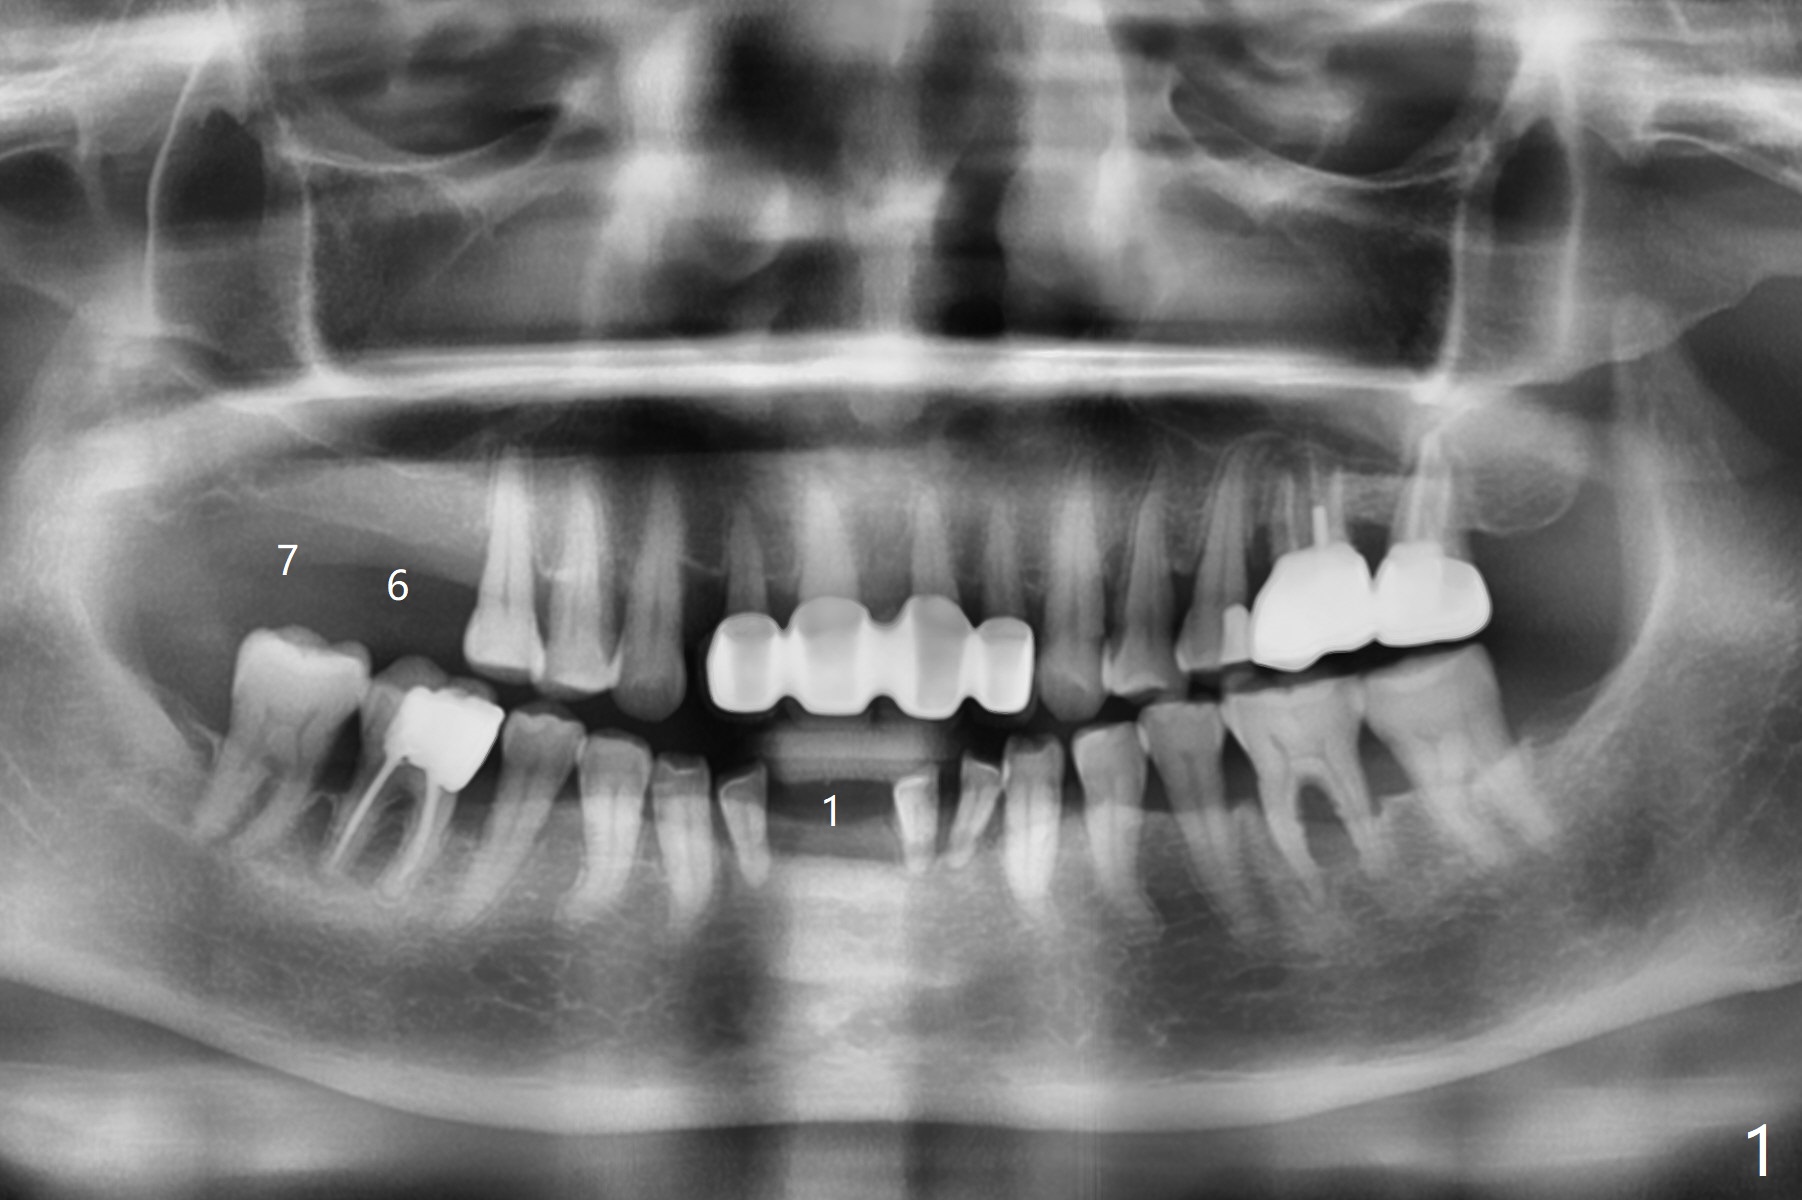

56岁女牙周炎,失去右上6,7以及右下1,后者缺牙间隙特别宽,其余切牙往颊侧移位(flare,病人不愿意拔除,图一)。右上植牙修复后(图二,三),下前牙种植(图四,五(选择窄植体)),建立正常覆盖,同时在邻近切牙唇侧植骨(图七,八:红线)。四-六个月后做局部矫正:使用植牙作为支抗将颊侧移位的前牙(牙冠)往舌侧推移(图七,八:蓝箭头),而牙根可能往唇侧移位(图六:红箭头),所以事先植骨(图七,八:红线)重要。矫正后3-3舌侧放置钢丝树脂固定。Jennifer: #25 implant and crown should be lingualized, as compared to the rest of the lower incisors (flared). After osteointegration, ortho will be conducted to correct the flaring using #25 implant as an anchor.